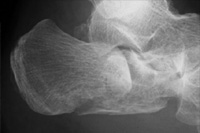

踵骨骨折では関節面が転位した例では,保存的療法では後遺症が残りやすいために手術を積極的行っています(図2-1)。また骨折型によって最小侵襲手術である経皮的骨接合術も選択しています(図2-2)。

図2-1

左:術前の左踵骨骨折

右:観血的整復術5年11カ月後